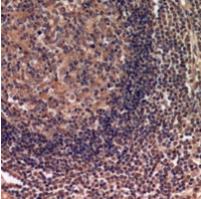

图片:

Immunohistochemical analysis of IDH3 alpha staining in human lymph gland formalin fixed paraffin embedded tissue section. The section was pre-treated using heat mediated antigen retrieval with sodium citrate buffer (pH 6.0). The section was then incubated with the antibody at room temperature and detected using an HRP conjugated compact polymer system. DAB was used as the chromogen. The section was then counterstained with haematoxylin and mounted with DPX.